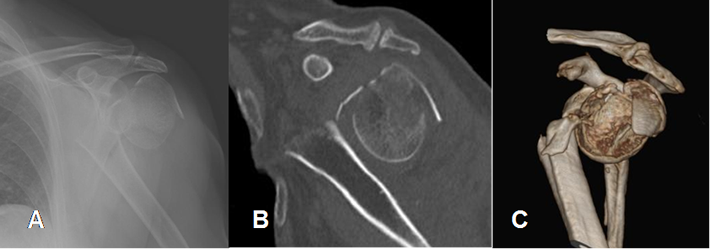

El TAC se utiliza para evaluar la extensión de la lesión y las reconstrucciones 3D, permiten hacer la planificación de la técnica quirúrgica. (1). (Fig 44).

Fig 44. Fractura de húmero reconstrucción 3 D.

A: Rx AP, B: TAC reconstrucción sagital y C: TAC reconstrucción 3 D. Fractura de la cabeza del húmero, con gran desplazamiento y angulación.